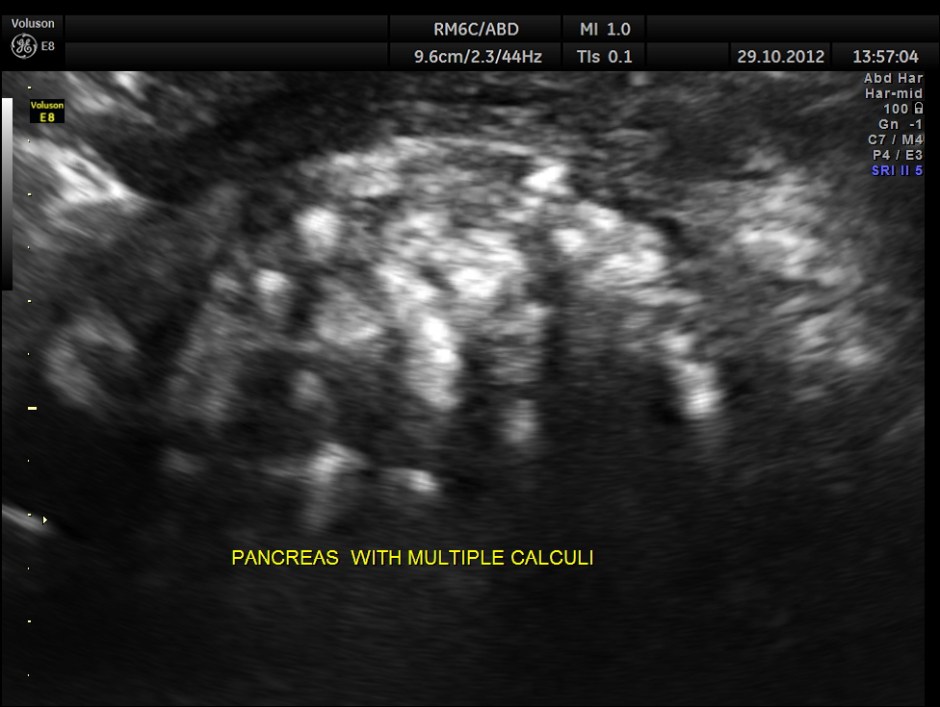

This was a 34 year old man with recurrent upper abdominal pain.

the next is the same image without the power doppler

When we have a doubt about the presence of calculi anywhere , colour and power doppler can clarify with the comet tail appearance appearing posterior to the calculi.

FIRST TIME SEEING A COMET TAIL IN PANCREATIC CALCULI